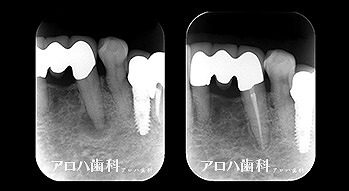

外科的歯内療法

case8

自費の補綴

頬側に瘻孔

case9

遠心口蓋側に限局性の深いポケット

上顎洞に波及している。

case10

左上に腫脹、圧痛。

根尖部に透過像

術前、術直後、予後

術前、術後